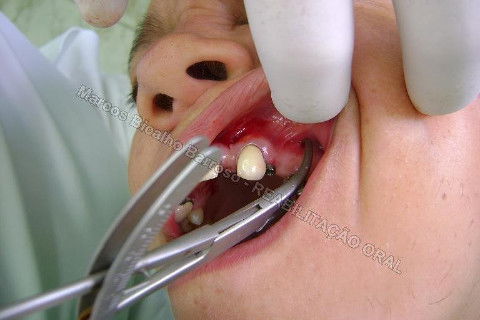

Paciente sexo feminino, 40 anos, queixava-se da situação da PPR superior, sem estabilidade, fraturas constantes nos dentes instalados. Sua vontade era resolver somente o problema da arcada superior, por questões financeiras. Logo no exame clínico inicial verifiquei a necessidade da reabiltiação inferior, pois este caso consistia em desarmonia oclusal severa, principalmente pela extrusão dos elementos 13,14 e 15 devido ausência de várias unidades inferiores. A proposta aceita pela paciente foi a instalação de 5 implantes na mandíbula + 5 implantes na maxila + tratamento endodôntico, osteoplastia e gengivoplastia nos dentes extruídos, incluindo núcleos metálicos e coroas em metalocerâmica (13,14,15). As coroas sobre implantes serão incialmente provisórias em resina fotopolimerizável e posteriormente metalocerâmica, de acordo com as possibilidades da paciente. Os procedimentos nos elementos extruídos serão apresentados em momento oportuno.